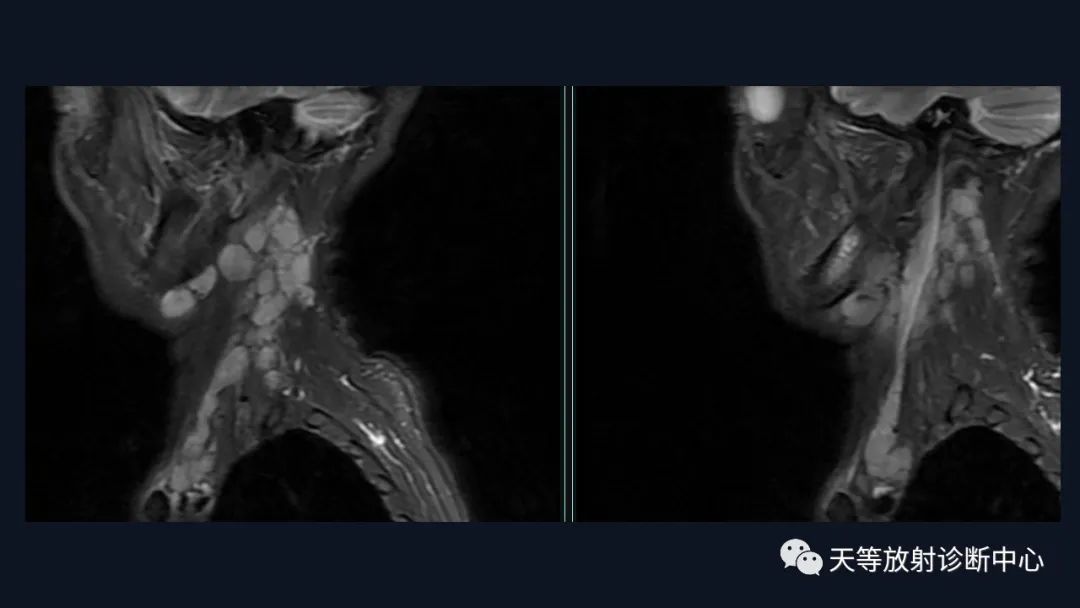

本病例影像学特点:

脑内占位的特点:

结合颈部、胸廓入口区及腋窝多发淋巴结肿大并相互融合。

综合考虑淋巴瘤